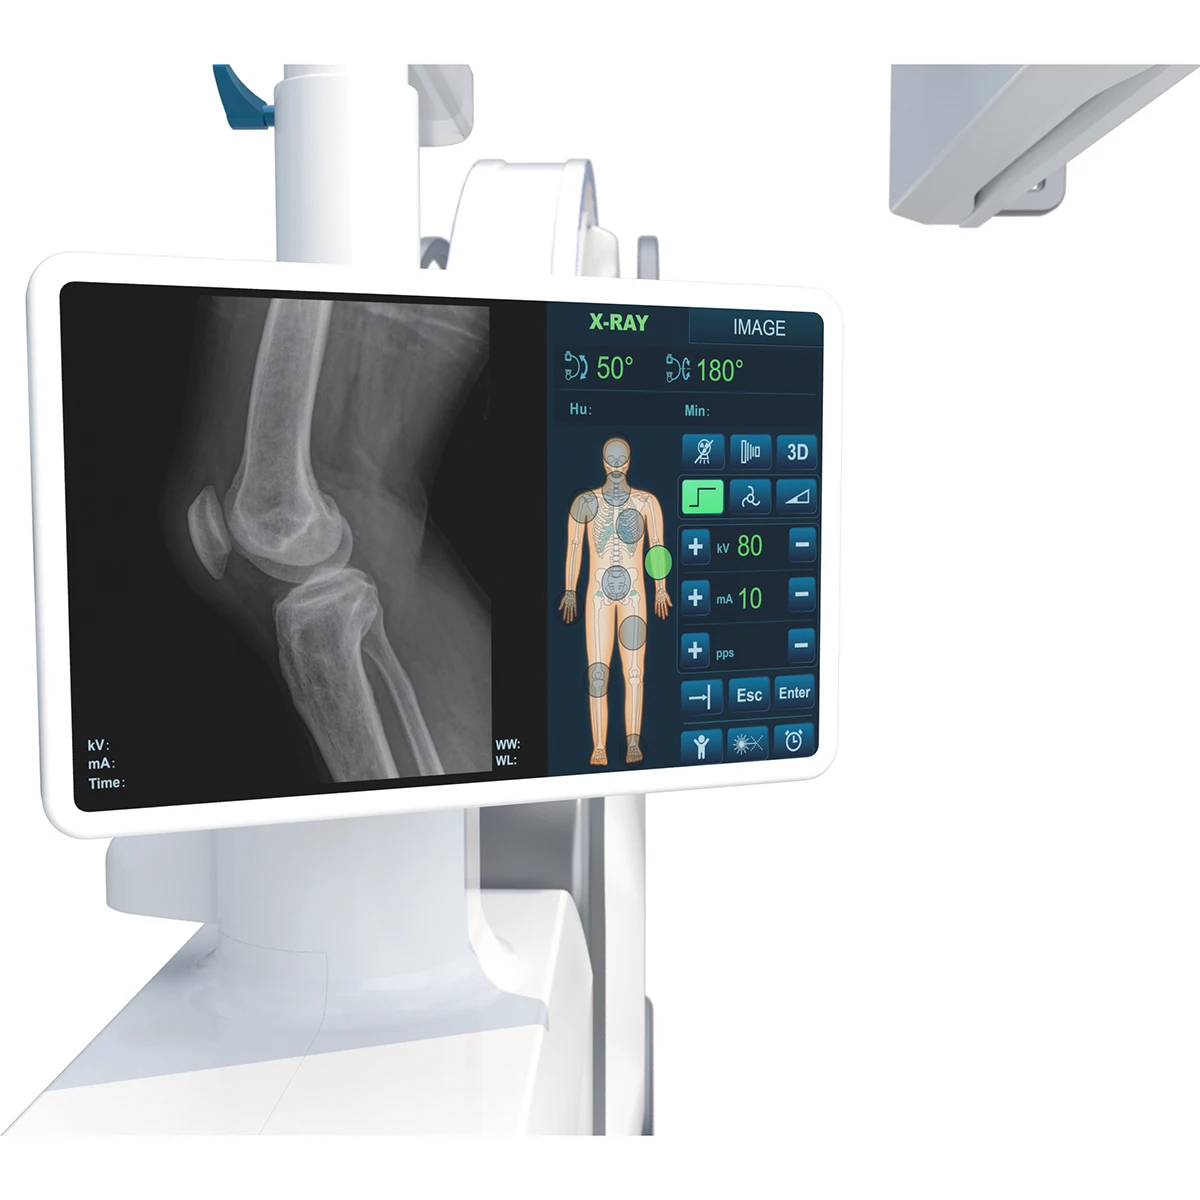

The system has a color human body graphic LCD touch screen, real-time adjustment of exposure parameters |

Tube voltage: 40-120kV |

Maximum tube current: 10mA( continuous perspective ); 50mA( pulse perspective) |

Maximum pulse acquisition rate 25f/s |

Maximum photographic current: 80mA |